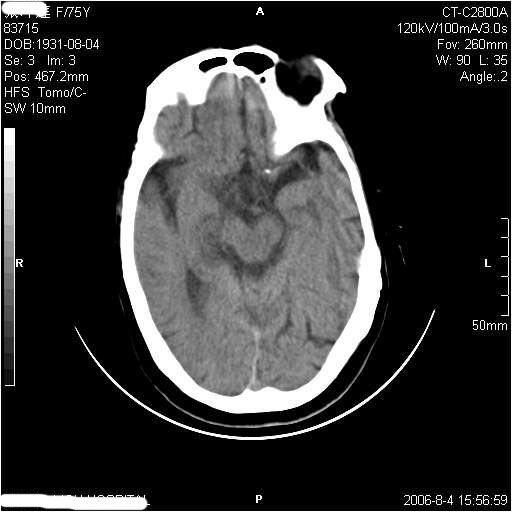

左侧偏瘫3天.

有摔倒外伤史,另看右侧灰白质界限.

1、该患者从脑实质表现情况看应该年龄较大了,双侧基底节区多发斑片状低密度灶,侧脑室旁白质密度减低,各脑室腔扩大,脑沟裂增宽加深,以上改变符合:皮层下动脉硬化性脑病。

2、上纵裂右侧梭形条状高密度影阴,边缘模糊,周围水肿带环绕,右侧脑室受压变形,有摔倒外伤史,多考虑:纵裂硬膜下血肿。